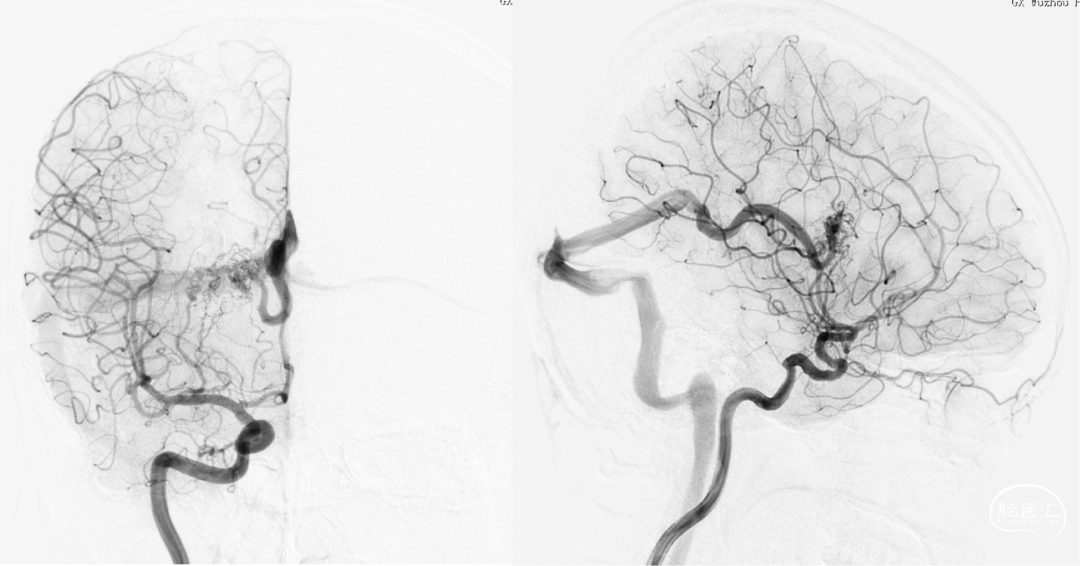

术前DSA:右侧基底节动静脉畸形,豆纹动脉供血,经大脑静脉、直窦、横窦、乙状窦引流

术前DSA